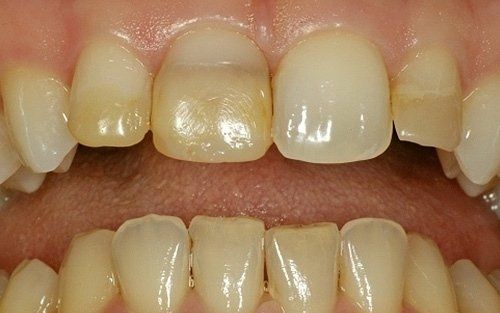

La paziente era, ovviamente, insoddisfatta dell'aspetto dei suoi denti

I restauri ultimati ad un controllo successivo

I restauri hanno subito una subito un intenso degrado sia nella forma che nel colore

I denti risultavano tutti vitali e dunque si è proceduto con terapie dirette molto conservative